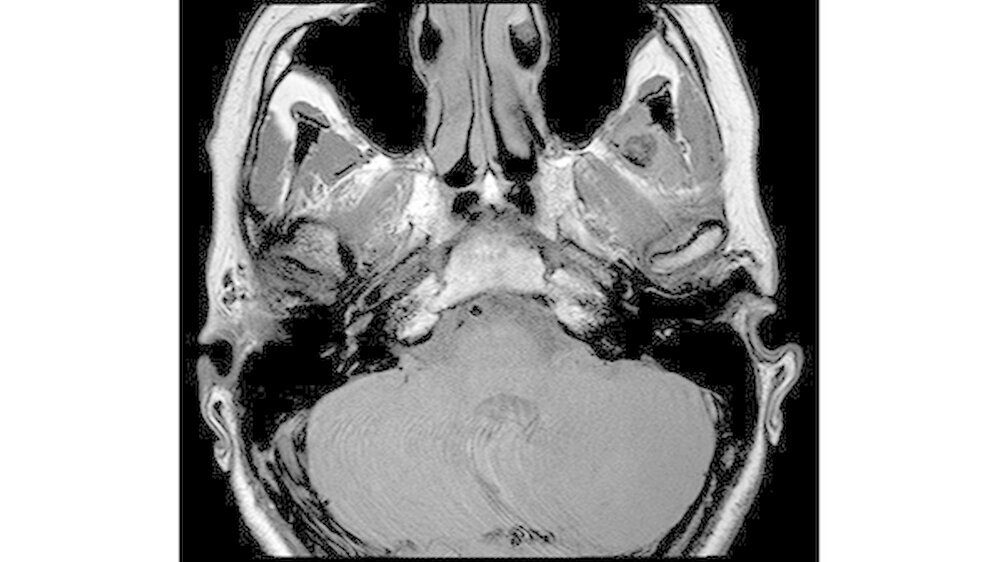

Das neun Tage später durchgeführte MRT zeigte keinen Anhalt für eine Läsion des Diskuskomplexes beidseits. Es wurde jedoch eine umschriebene, teils T2-hyperintense sowie kräftig randständig kontrastmittelaufnehmende Läsion im M. pterygoideus medialis links (axial bis zirka 1,0 cm) angrenzend an den Processus muscularis vereinbar mit einem kleinen intramuskulären Abszess beschrieben (Abbildungen 3 a und b).

Des Weiteren erschien der M. pterygoideus medialis links in seinem ganzen Verlauf ödematös verändert, jedoch ohne Anhalt für eine Beteiligung der umliegenden Strukturen wie dem M. pterygoideus lateralis.